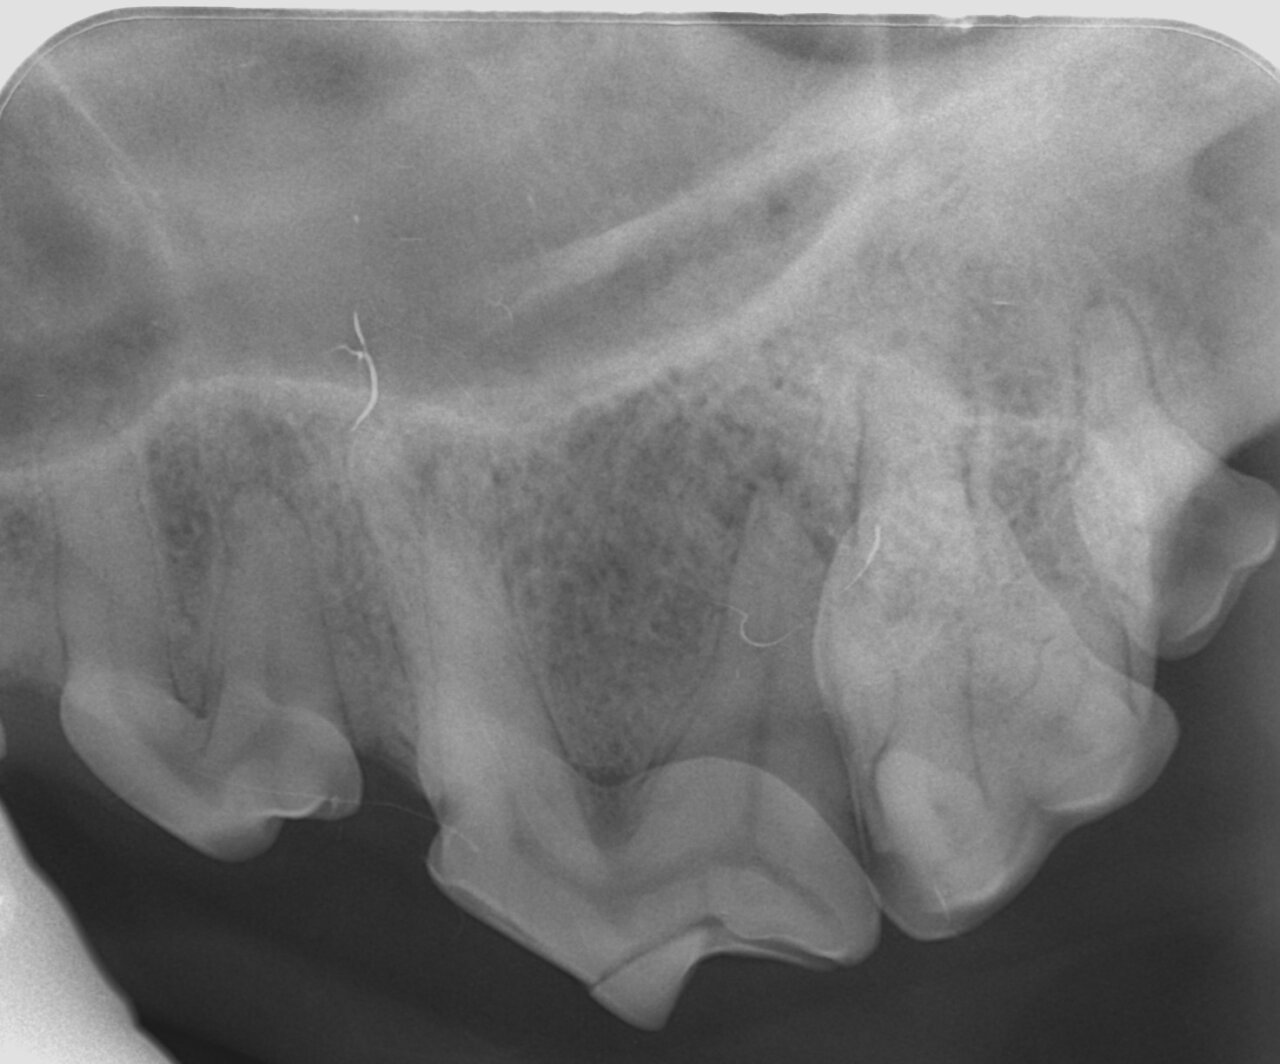

Para el diagnóstico de la EP, además de realizar un examen periodontal a través del sondaje debemos apoyarnos en la radiografía, ya que nos proporciona información acerca de la cantidad de pérdida ósea existente, así como del patrón que sigue esta pérdida (horizontal y/o vertical). En dientes multirradiculares, podemos servirnos de la furca para evaluar la pérdida de hueso, ya que aparecen áreas radiolúcidas bajo la bifurcación radicular a medida que se produce la destrucción ósea.

De acuerdo a esta pérdida del hueso alveolar detectada a nivel radiológico, clasificaremos la EP en cuatro grados:

- Grado 2 (PD2): pérdida del soporte óseo menor al 25 % (imagen 7).

- Grado 3 (PD3): pérdida del soporte óseo de un 25-50 % (imagen 8).

- Grado 4 (PD4): pérdida del soporte óseo mayor de un 50 % (imagen 9).